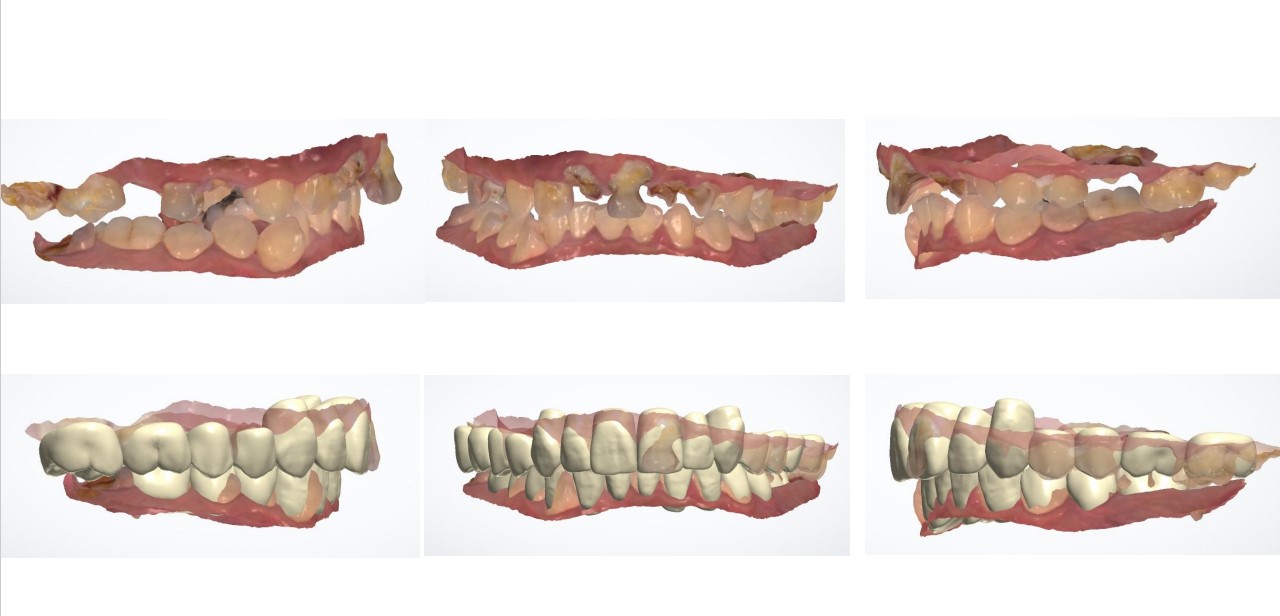

術前術後口內模擬

術後外觀模擬

治療後 :套上假牙套+無牙根缺牙處靠牙橋復型,洗牙減緩牙齦發炎

牙根穩固了,牙周健康了,猶如樹根穩穩地抓住肥沃土壤,樹木自然能成長茁壯!!! 套上牙套調整咬合,恭喜您畢業了!!!!